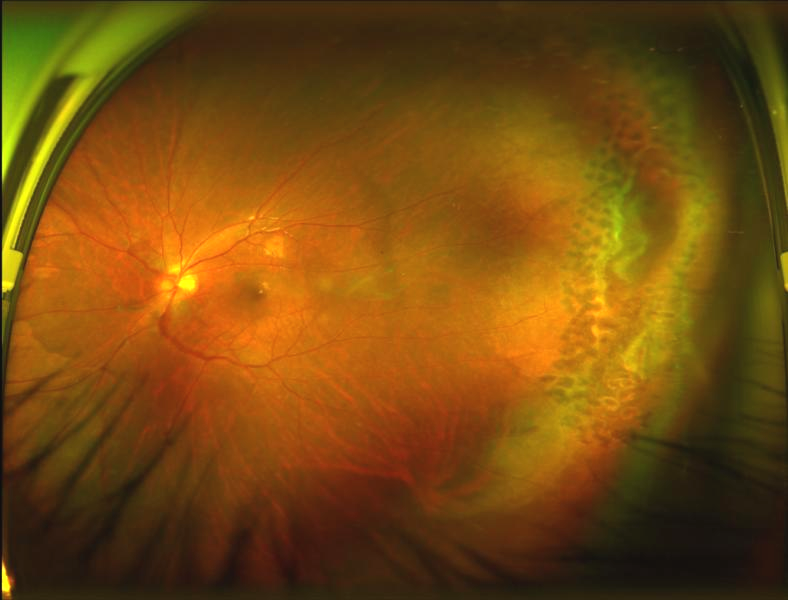

術后觀察幾天,小曾的傷眼視力已經有了逐步提高,病情穩(wěn)定,現已順利出院。小曾及家屬均對陳燕和江國華副主任醫(yī)療組的手術效果非常滿意!

術后24天

球囊取出術后